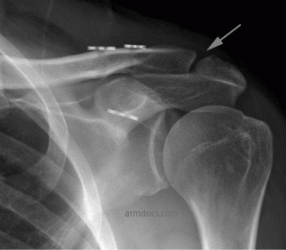

a. Complete separation of the acromioclavicular joint